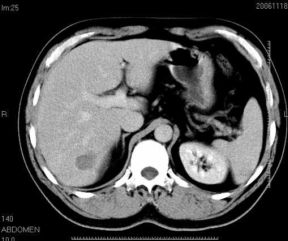

男性,48岁

肝内占位,性质?

肝内多发低密度占位病变,边缘清晰,无强化,肝转移瘤可能

肝内多发低密度占位病变,边缘清晰,无强化,肝转移瘤可能大,请将胃喝水充盈以后再扫描看看,我看大弯侧胃壁较厚。

肝内多发不规则形状低密度灶,强化不明显,考虑转移,积极查找原发灶

患者,男性,48岁

肝内多发低密度类圆形病灶,边缘清晰.增强无强化.

意见:1,考虑多发转移瘤;

2,囊肿与血管瘤不排除.

肝内多发不规则形状低密度灶,强化不明显,考虑转移,找找原发灶

1肝内多发低密度影,考虑:转移瘤 2胃大弯侧胃壁明显增厚,建议胃镜检查除外胃癌

我认为先考虑原发性肝癌。

首先考虑转移瘤。

多考虑转移瘤

转移瘤?